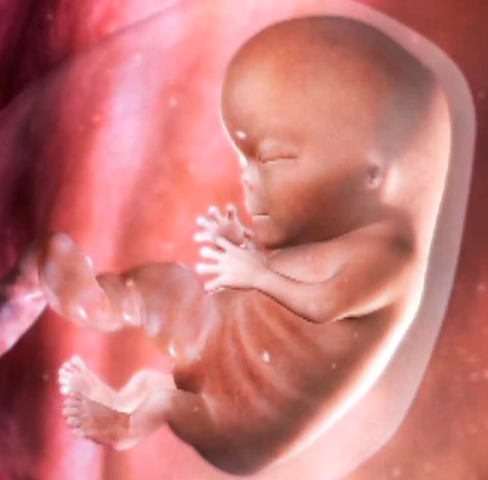

By week eleven, the baby has begun developing ears, toes, an upper lip, and twenty teeth. Also during this week the genitals of the baby have begun to develop.

By week twelve,the baby's facial profile, brain, and vocal cords are fully developed. Also by this week you'll be able to hear your baby's heartbeat.